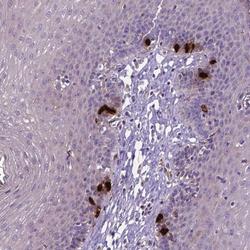

- Main image

- Experimental details

- Immunohistochemical staining of CCER2 in human esophogial tissue shows strong cytoplasmic and nuclear positivity in a subset of cells. Samples were probed using a CCER2 Polyclonal Antibody (Product # PA5-64427).